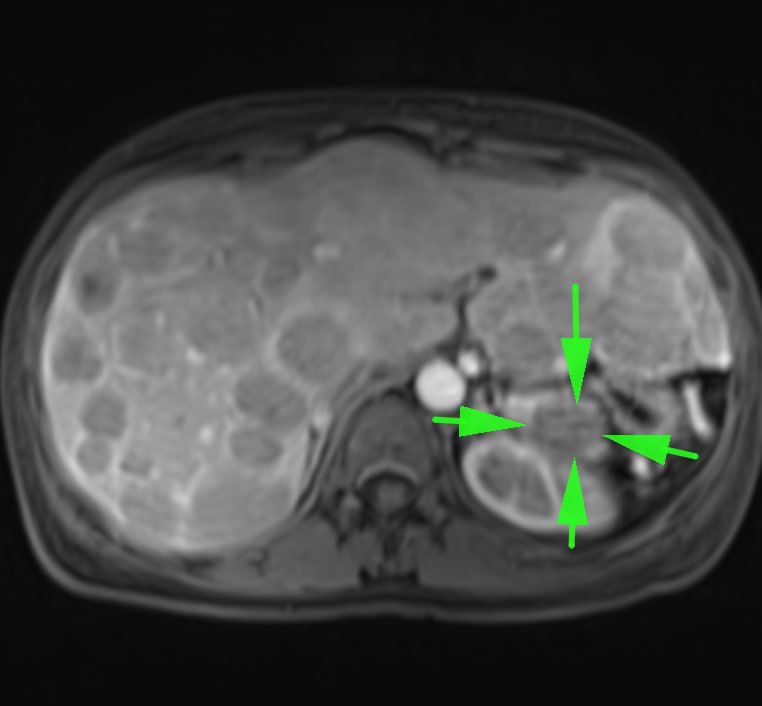

Одно из самых паскудных проявлений злокачественной опухоли - перитонеальный карциноматоз.

Средняя выживаемость при нем по одним данным составляет от 2,3 до 9 месяцев, по другим - варьирует от 11 до 17 месяцев при первичной опухоли, и зависит от стадии первичной опухоли при вторичном (стадии 0-2 - 5-10 месяцев, стадии 3-4 - 2-3,9 месяцев). Расположение первичной опухоли также может влиять на показатели выживаемости: при колоректальной карциноме средняя продолжительность жизни составляет 6,9 месяцев. Средняя продолжительность жизни при опухоли желудка составляет 6,5 месяцев.

Девушка 72 лет с карциноматозом брюшины, известно, что была гистерэктомия, а при перитонеальном карциноматозе, вызванном раком эндометрия средняя продолжительность жизни не превышает 12 месяцев, хотя при проведении циторедуктивной хирургии в сочетании с гипертермической внутрибрюшинной терапии описывают случаи продолжительности жизни и до 3 лет (интересно, что саудиты такое опубликовали, можно ли верить? Хотя, французы опубликовали, что после такого лечения аж трое пациентов прожили 7, 23 и 39 месяцев).

А у вас в местечке проводят такую терапию?